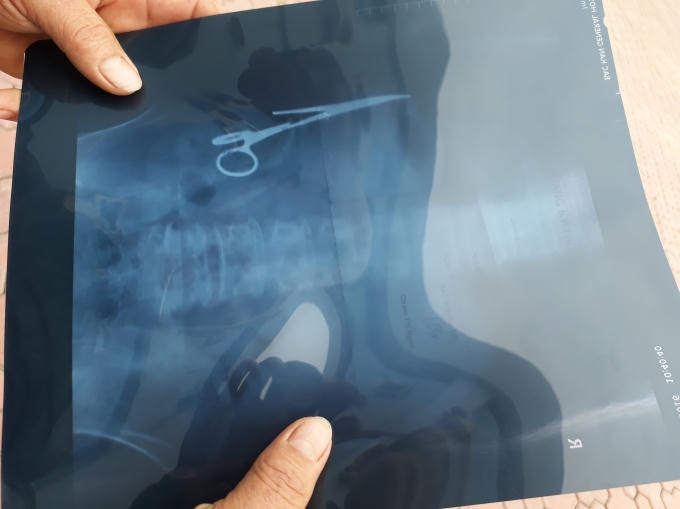

Như Phapluatplus.vn đã thông tin, do bị tai nạn ông Ma Văn Nhật (SN 1962), trú tại xã Bình Trung, huyện Chợ Đồn, tỉnh Bắc Kạn đã vào Bệnh viện Gang thép Thái Nguyên để khám. Tại đây, các bác sĩ bệnh viện đã phát hiện có một dị vật dài 15 cm nằm trong ổ bụng. Vật thể lạ nằm trong bụng ông Nhật được xác định là một chiếc panh chuyên dùng để mổ, sử dụng trong ngành y.

Theo ông Nhật, sau một vụ tai nạn giao thông vào năm 1998, ông bị chấn thương ở mạng sườn và phải vào cấp cứu tại bệnh viện. Sau khi được tiến hành các biện pháp sơ cứu ban đầu tại Bệnh viện huyện Chợ Đồn, ông đã được chuyển tới Bệnh viện Đa khoa tỉnh Bắc Kạn.